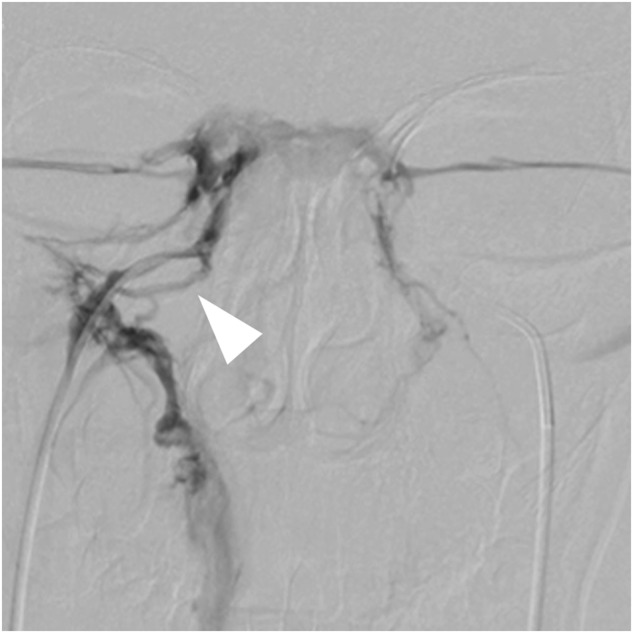

Clinical characteristics were compared between 11 true positive and 5 false negative patients (Table 3). The differences of age, duration of disease, height, height SDS, weight, weight SDS, BMI, ACTH level, 24 h UFC, sex, and proportion of patients with tumor on the right side between the two groups of patients were not significant. Images of angiography were also examined, and plexiform IPS was found in some true positive patients (Fig. 2), while no anatomical variation of IPS was detected among the false negative cases. However, sampling lateralization rate before stimulation was 20.0% (1/5) among false negative patients and 81.8% (9/11) among true positive patients, the difference of which was significant (p = 0.036). The absence of sampling lateralization was related to false negative cases. Besides, baseline IPS:P ratio was positively correlated with the baseline ACTH concentration at the dominant IPS (ρ = 0.909, p < 0.001), and the baseline ACTH concentration at the dominant IPS was significantly lower (p = 0.001) among the false negative patients. In addition, true positive patients tended to had a higher frequency of actual tumor position on the left side (p = 0.093).

Fig. 2.

The angiography of inferior petrosal sinus in a true positive patient. The arrowhead indicates the plexiform IPS